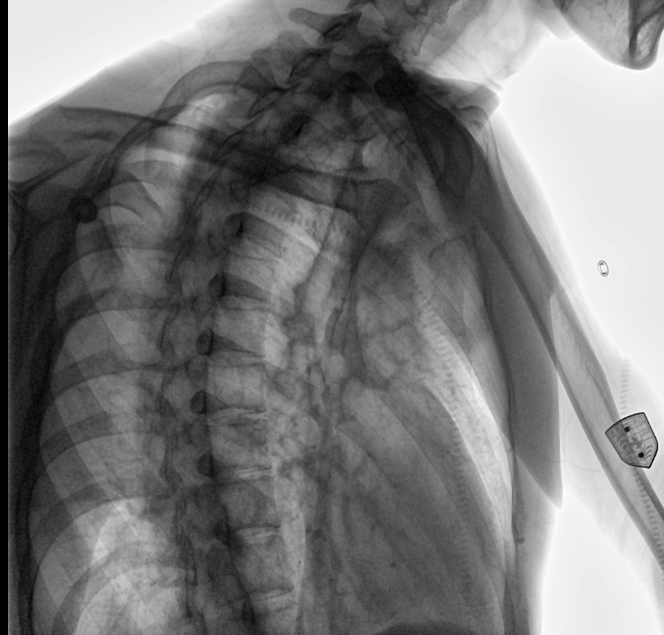

安健科技動態(tài)平板DR-DTP571

位于衡水市中醫(yī)醫(yī)院的動態(tài)平板數(shù)字化X射線系統(tǒng)DTP571具備高速高清點片功能。這是一款對放射科十分友好的產(chǎn)品。因為它把高速和高清點片結(jié)合,既能方便影像技師有效地抓拍需要的病灶的影像,又能給予影像醫(yī)生清晰的影像進行診斷

動態(tài)觀察診斷,實時高清點片